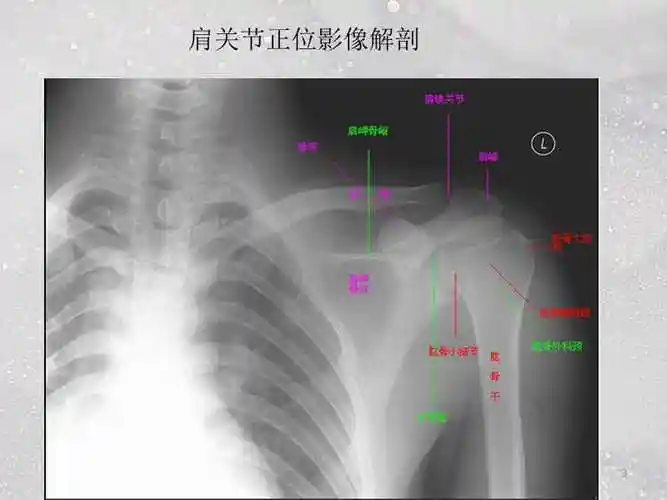

肩关节的摄影体位ppt课件